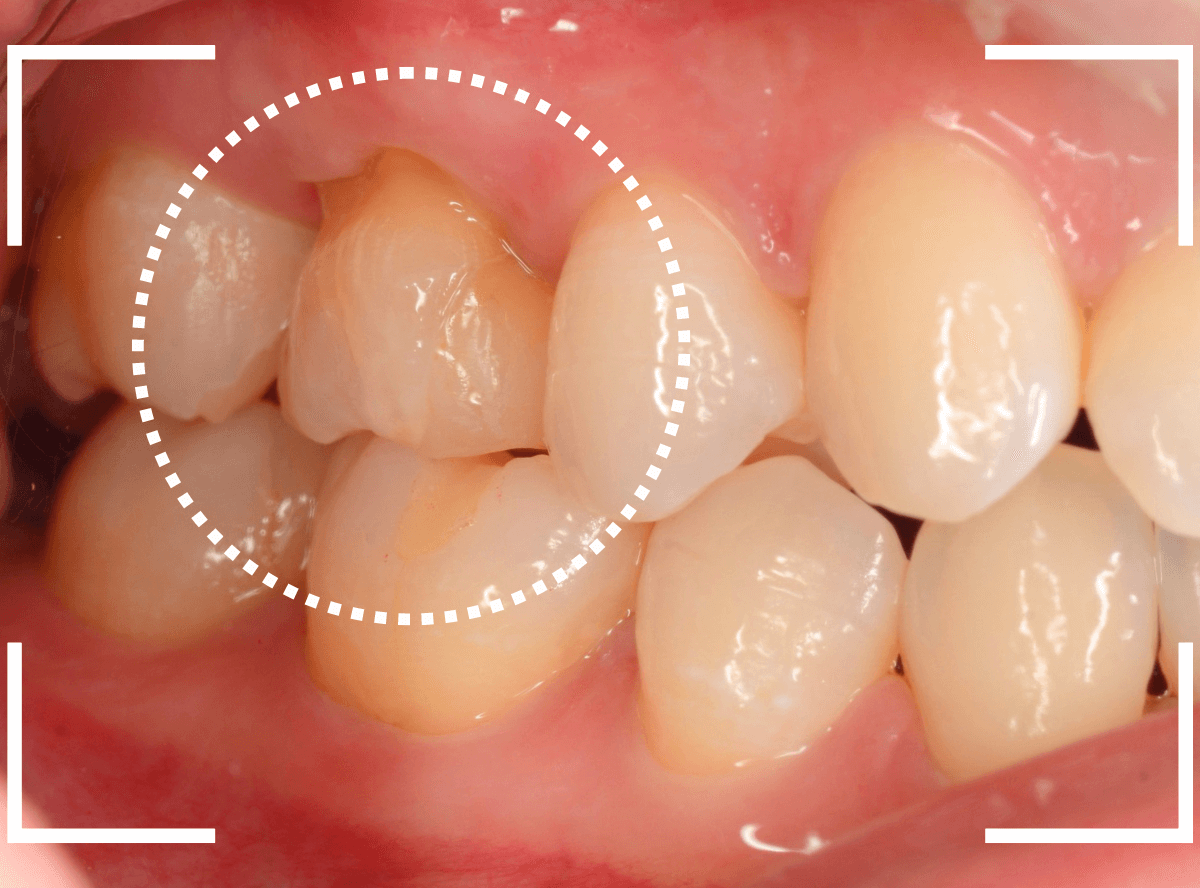

Case.29

舌のそばの虫歯とセラミック治療

下の奥歯が虫歯になった患者さんのケースです。

〇部が虫歯の部分です。

写真で見てわかるように、常に舌が歯に触っているような状況です。

このような場合、虫歯を見つけづらいですし、治療の難易度もあがります。